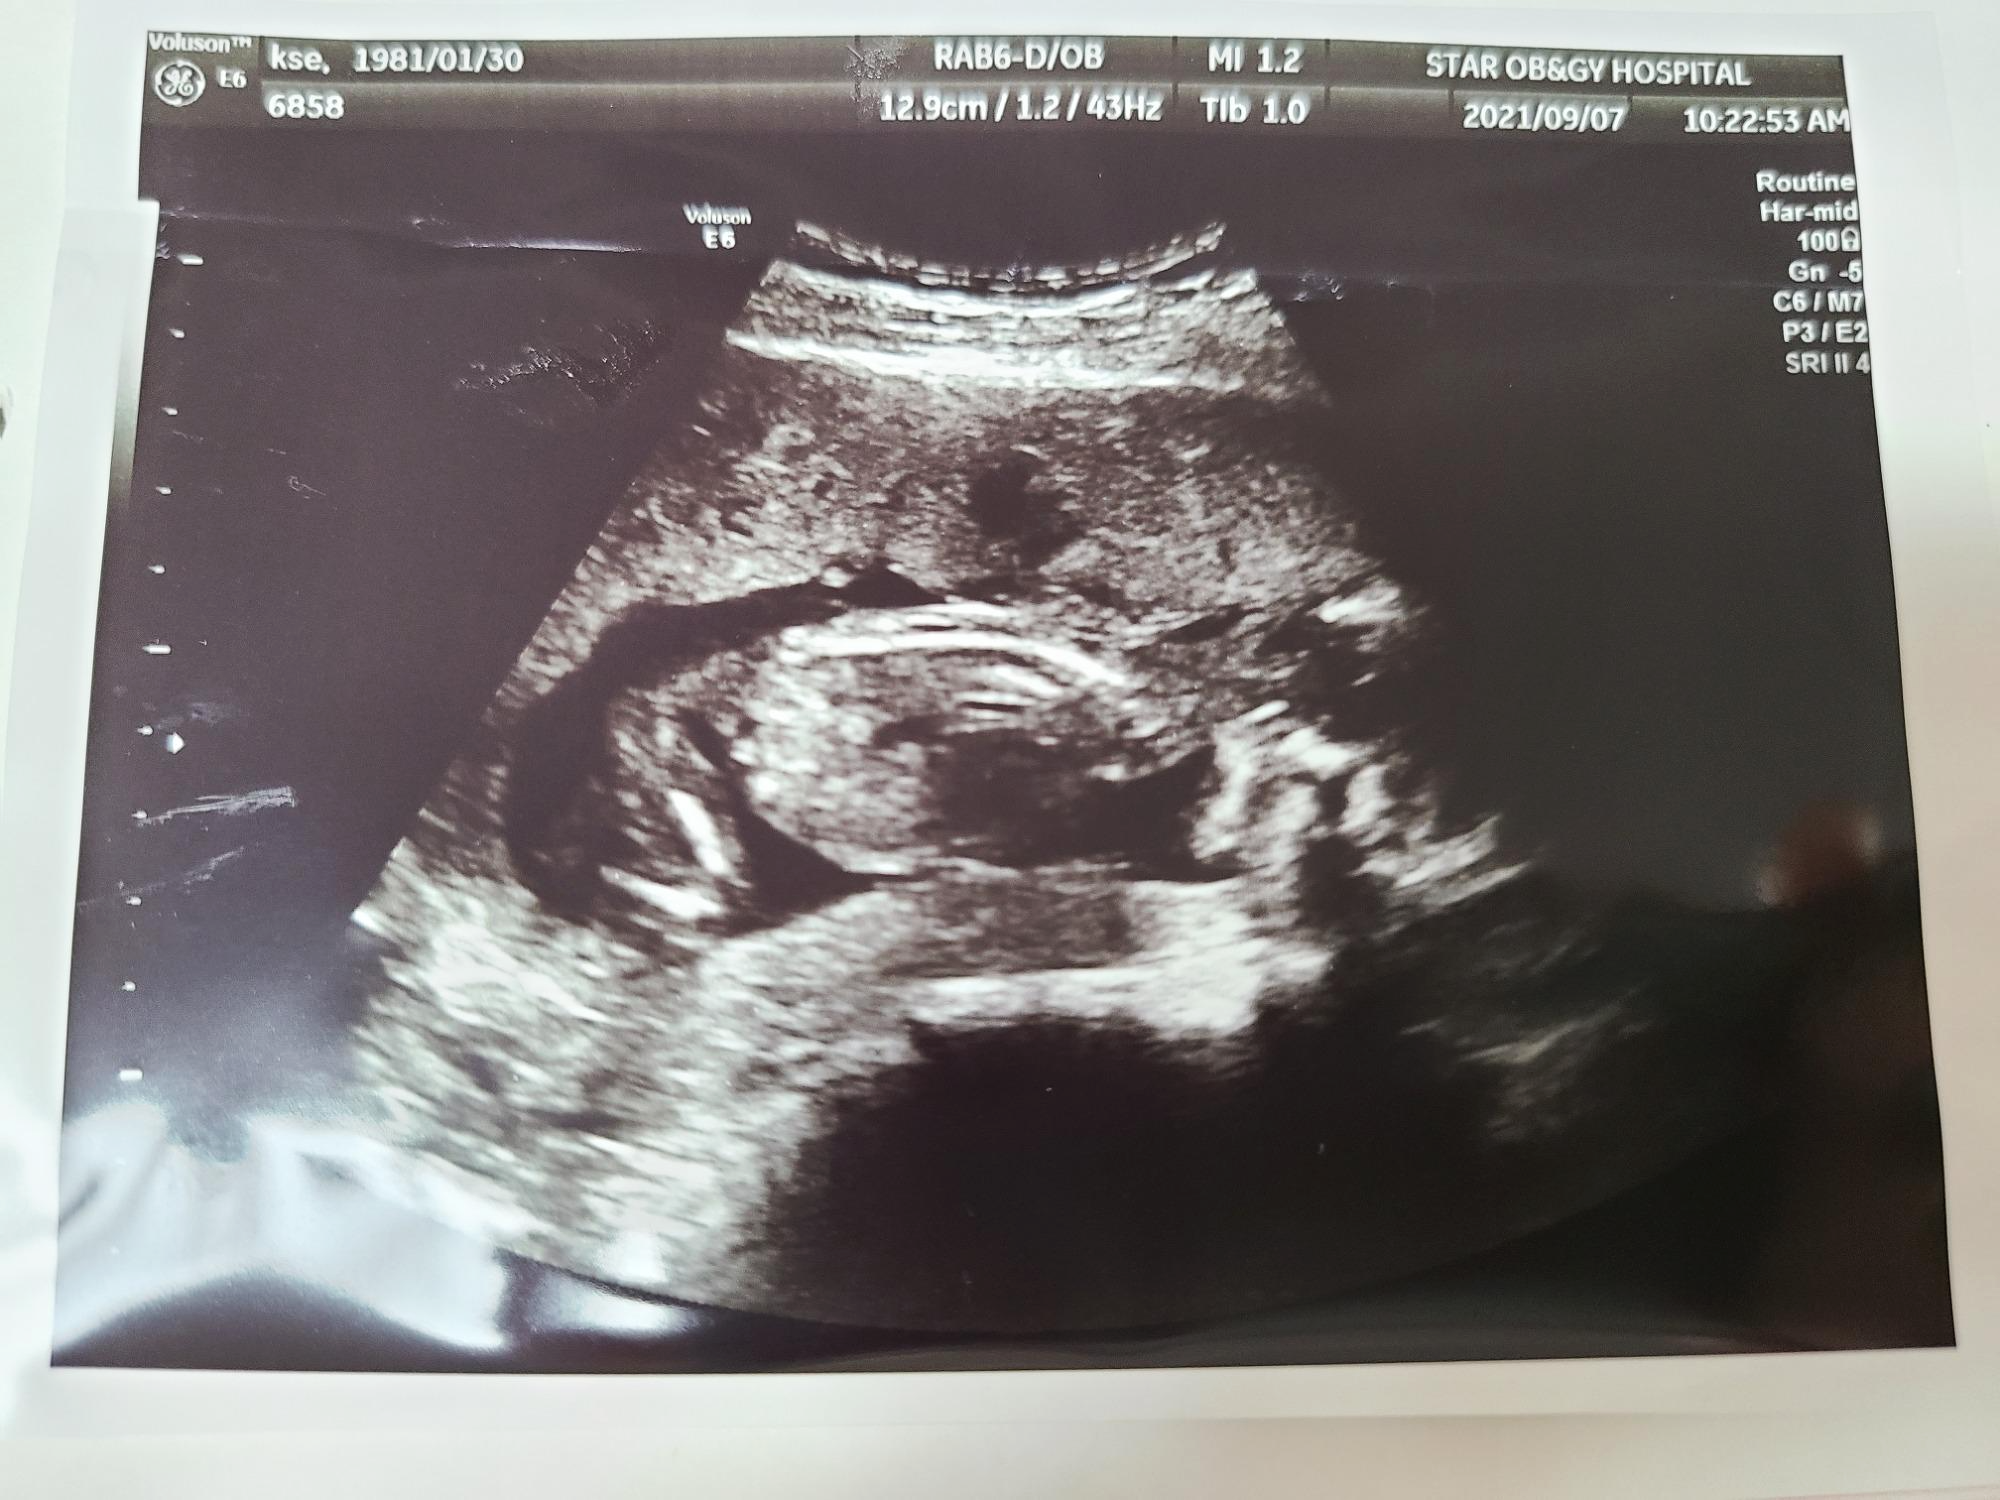

떨리는 마음으로 지난 8월 10일 12주 차에 병원에 방문해 1차 기형아 검사를 받았어요.

20주에 정밀 초음파를 보며 의사 선생님께서 기형아 검사 결과지를 살짝 화면에 띄워주셨는데 기형아라고 판단할 수 있는 기준점보다 모두 다 낮은 결과가 나왔더라구요.